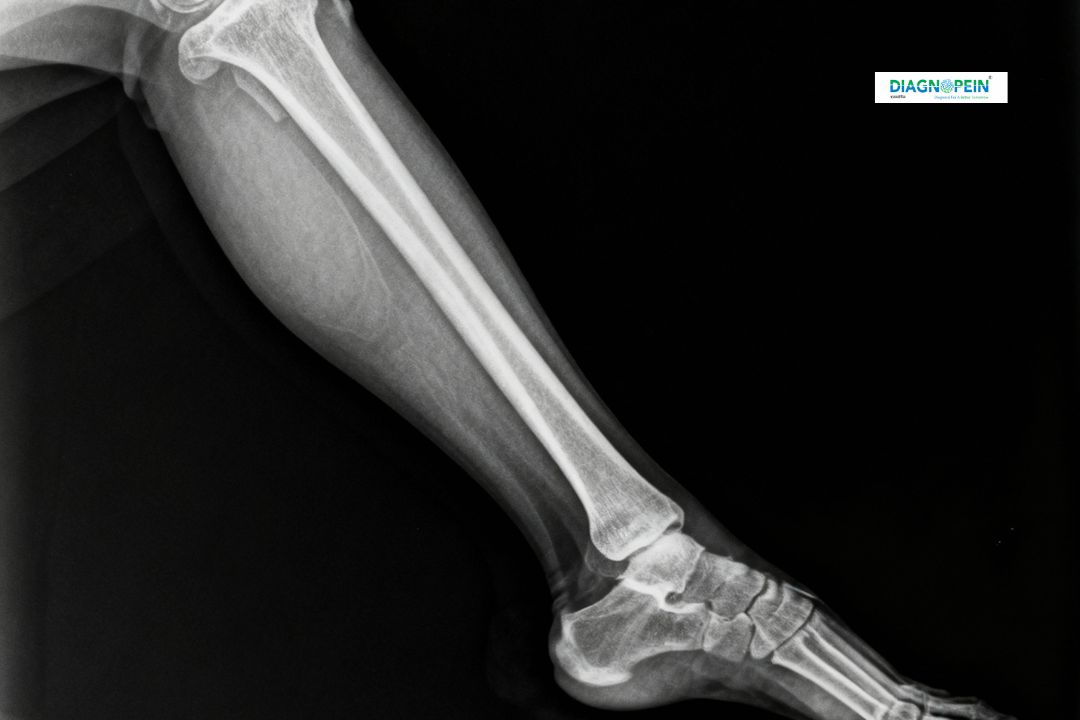

At Diagnopein in Karad, we provide advanced digital X-Ray Left Leg Lateral (LAT) View imaging for accurate diagnosis of bone injuries, fractures, and joint conditions. This specialized imaging technique helps visualize the left leg’s bone structure from a side angle, offering detailed insights for orthopedic assessments and surgical planning.

The X-Ray Left Leg LAT View is a non-invasive diagnostic test that uses safe, low-dose radiation to create clear images of the leg’s bones including the femur, tibia, fibula, and knee joint. With modern X-Ray machines and expert radiologists, Diagnopein ensures accurate results and quick turnaround times for patients in and around Karad.

An X-Ray Left Leg LAT View in Karad helps evaluate several diagnostic parameters:

1. Bone alignment and joint orientation

2. Fracture lines or bone discontinuities

3. Bone density and thickness

4. Soft tissue shadows and signs of swelling

5. Post-surgical implants or fixation alignment

These observations help doctors in Karad determine the type and extent of bone or joint problems, ensuring the correct treatment plan for patients.